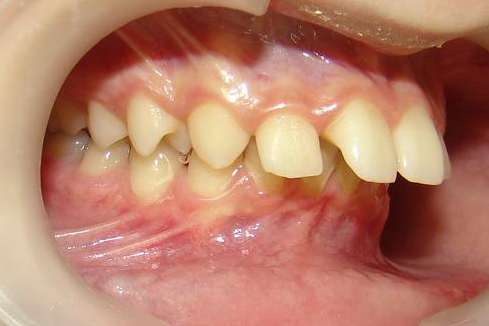

Начну с самого простого. Мальчик, 6 лет. Носил съемную плстинку 4 мес. В таком возрасте брекеты еще, как правило, не используют.

А это уже молодой человек 10 лет. Тоже получилось справиться без удаления. Хоть оно и было показано. Но мальчик очень упорно носил специальные аппаратики и резиночки. Покажу со всех сторон. Этот случай победил в конкурсе на конференции